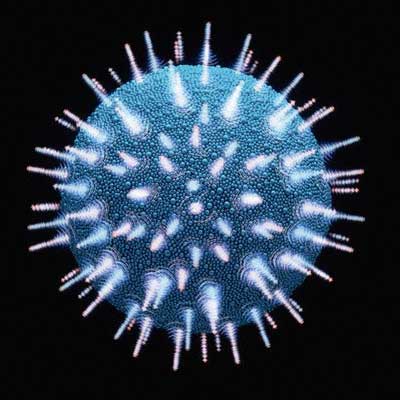

Pesquisadores da Universidade de Ciência e Saúde de Oregon, nos EUA, desenvolveram uma vacina contra o HIV.

Ainda de acordo com o site a vacina está sendo testada numa forma do vírus que ocorre em primatas, o vírus da imunodeficiência símia (SIV, na sigla em inglês).

Ainda de acordo com o diretor esta pesquisa sugere que certas respostas do sistema imune provocadas pela vacina podem remover completamente o HIV do corpo, curando assim o portador do vírus.

No estudo, cerca de 50% dos macacos infectados que receberam o patógeno acabaram eliminando todos os traços do vírus, ou seja, foram curados “funcionalmente”, explicou Picker.